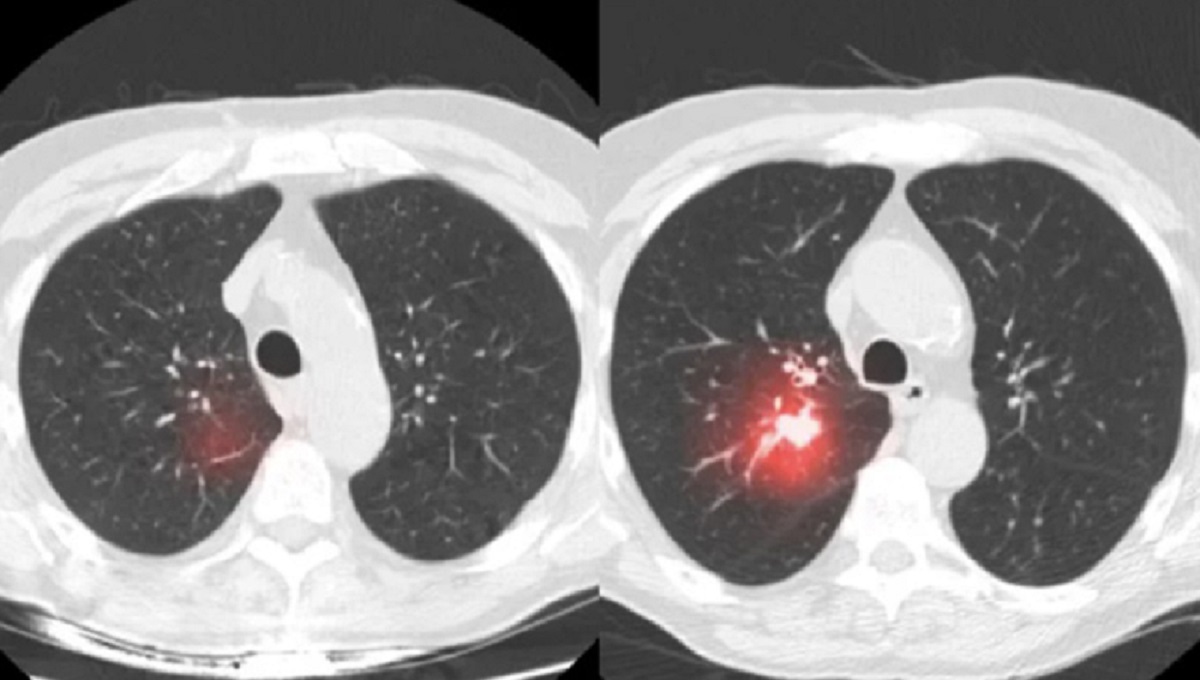

Chụp CT phổi liều thấp là phương pháp giúp phát hiện bệnh ngay khi chưa có dấu hiệu, hoặc biểu hiện bất thường ở phổi. Đây là kỹ thuật chụp hiện đại tiên tiến hơn cách thức chụp X-quang thông thường, và sử dụng lượng tia X vừa phải.

Kỹ thuật này tạo ra hình ảnh cắt lát tái hiện lại hình dáng phổi (mô, cơ quan, mạch máu,..). Kỹ thuật có thể tạo ra nhiều lát cắt hình ảnh dạng 2D hoặc 3D, giúp các bác sĩ theo dõi được tình trạng phổi của người bệnh.

Chụp cắt lớp vi tính (CLVT) liều thấp còn có tên gọi là chụp CT phổi liều thấp. Phương pháp này là lựa chọn tối ưu của các bác sĩ khi muốn theo dõi cho tiết các bất thường ở phổi. Đặc biệt hơn, kỹ thuật này còn giúp phát hiện các khối u phổi ở giai đoạn đầu.

Phát hiện khối u sớm: hiển thị rõ hình ảnh khối u ung thư khi có kích thước rất nhỏ (giai đoạn đầu).